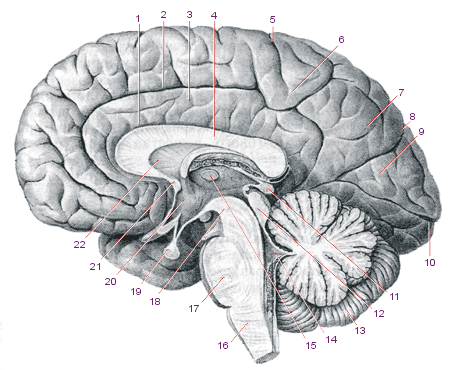

Необычные объекты: Переднее продырявленное вещество